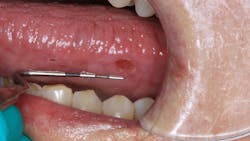

Patient: 64-year-old female

- Red, inflamed tissue throughout the oral cavity

- Large, ulcerlike lesions on the right and left lateral borders of the tongue

- Well-defined edges with a slightly concave red center that is tender to palpation

- Vestibular tissue sloughs and hemorrhages easily

- Angular cheilitis observed